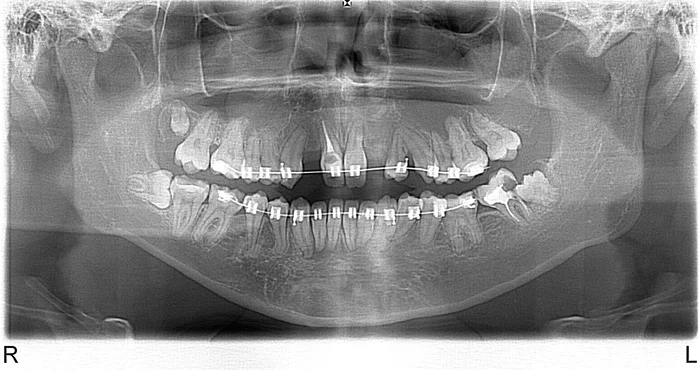

Фото: через некоторое время та же пациентка - в правом углу можно наблюдать, как зуб мудрости разрушает соседний зуб

Также показанием к удалению являются случаи в которых зуб мудрости прорезался не ровно, а под наклоном, при этом он уперся своей жевательной поверхностью в пришеечную область соседнего с ним зуба. В таком случае возможно развитие кариозного процесса в этом зубе. При этом процесс развивается под десной и его совершенно не видно, он никак себя не проявляет. Иногда, если пациент несвоевременно обращается за медицинской помощью, разрушение соседнего зуба столь велико, что нет никакой возможности сохранить и отреставрировать его. И тогда приходится удалять зуб мудрости вместе с соседним зубом.